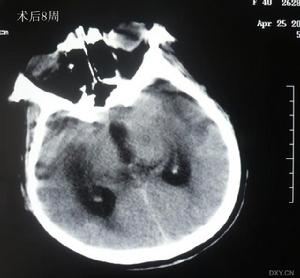

(1)非增強掃描:病灶主要位於基底節區、丘腦、內囊、腦幹或放射冠、側腦室旁,呈圓形或橢圓形低密度灶,邊界清楚、直徑2~20mm,占位效應輕,一般僅為相鄰腦室受壓,多無中線結構移位。梗死區密度約於4 周后接近腦脊液密度,並呈現萎縮性改變,即同側側腦室和(或)鄰近腦池、腦溝局限性擴大,中線結構可有輕度的同側移位。

(2)增強掃描:梗死後3 天~1 個月,病灶可呈均勻或斑片狀強化,以2~3周時此效應最為明顯。待病灶密度與腦脊液密度相等時則不再強化。

(9)外科治療:幕上大面積腦梗死有嚴重腦水腫、占位效應和腦疝形成徵象者,可行開顱減壓術;小腦梗死使腦幹受壓導致病情惡化的病人通過抽吸梗死小腦組織和後顱窩減壓術可以挽救生命。